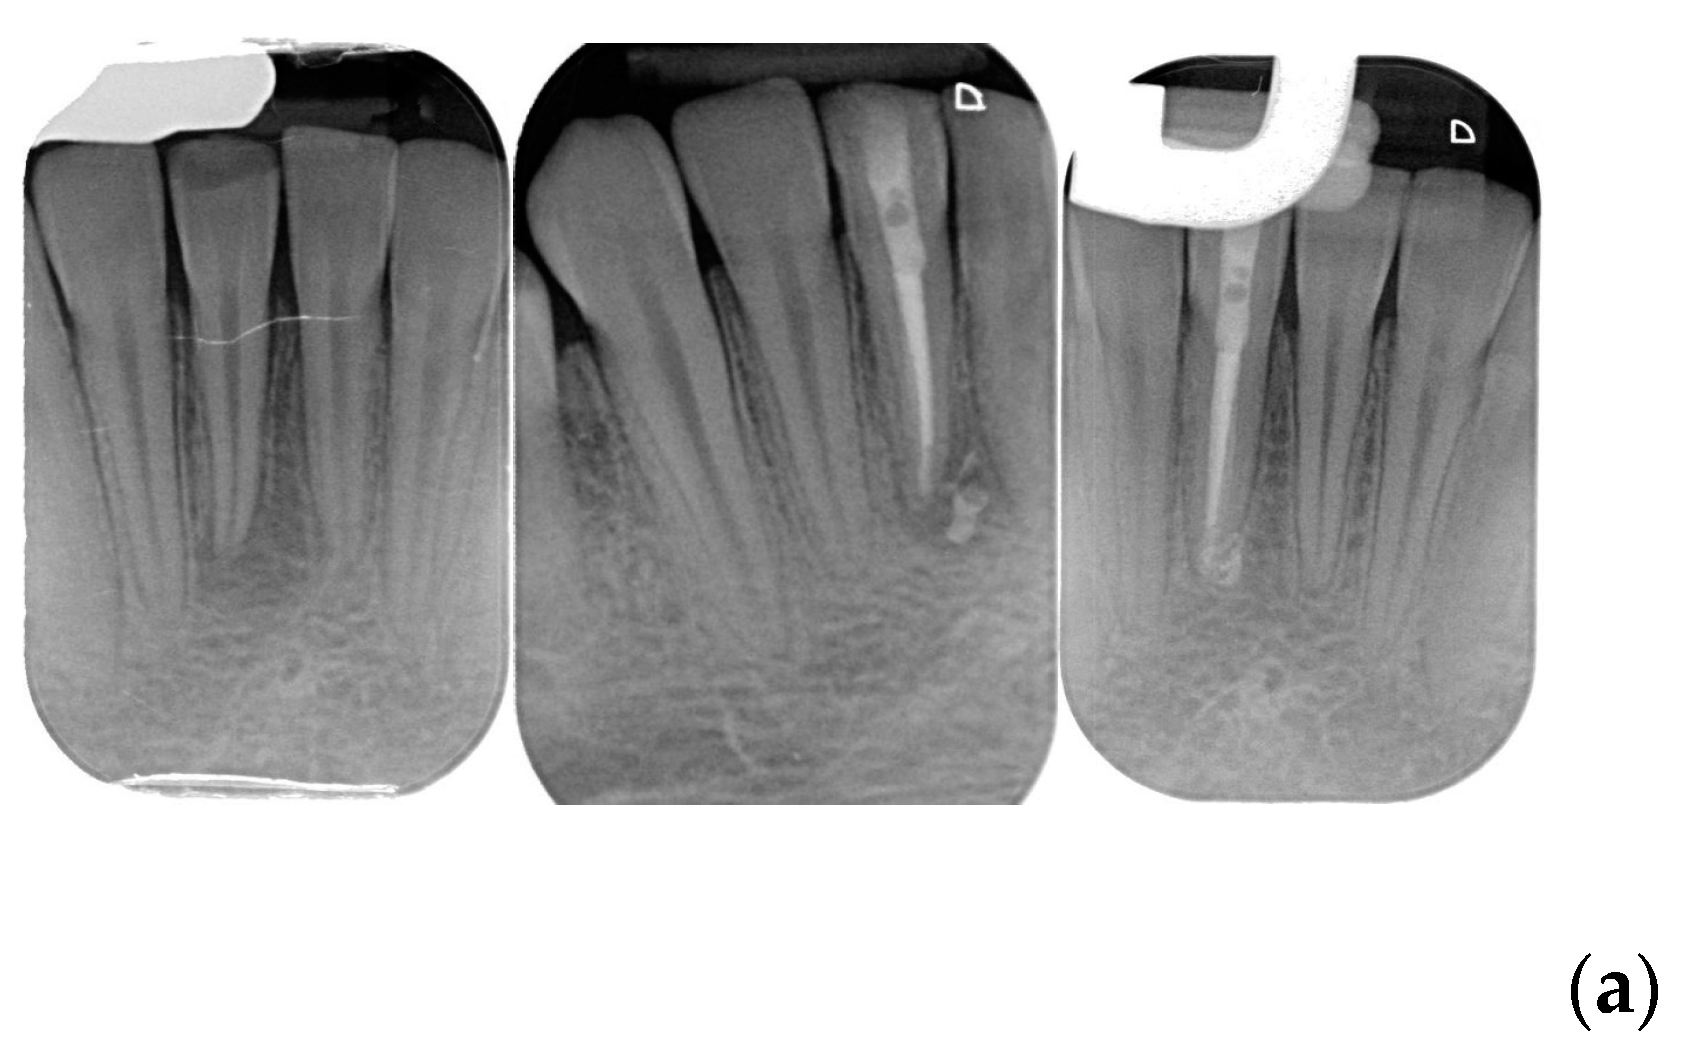

The clinical evaluation ‘success’ was referred to healed and healing categories and ‘failure’ to the not-healed teeth was classified as failure. Figure 1 show examples of each category. When a disagreement on the radiographic and/or clinical evaluation between the two evaluators was present, a discussion was made and a final consensus was reached. Examples of each outcome category are shown in Figure 1a–d.

Figure 1.

(a) Healed lower incisor at 12 months recall. (b) Healed upper first molar at 18 months recall. (c) A lower second molar in healing process after 6 months. (d) Not healed first upper bicuspid at 8 months recall.